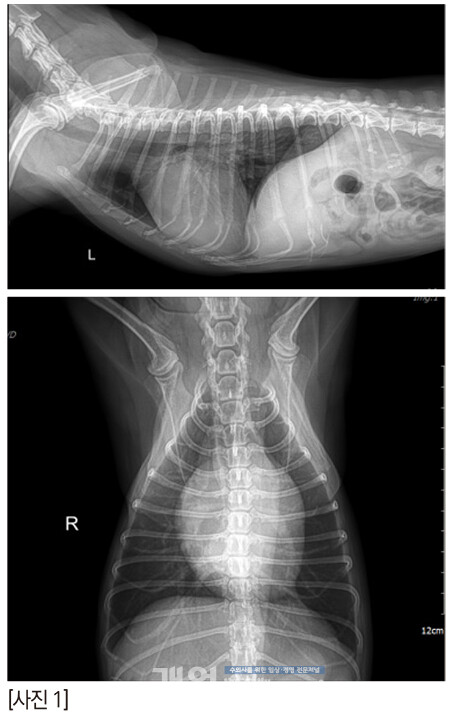

짱아의 방사선은 이렇다. 오랫동안 MMVD B2 로 유지되고 있다.

콩팥에는 결석이 있고, 복부초음파에서 콩팥은 점점 나이가 들어가고 있는 것은 확실하다.